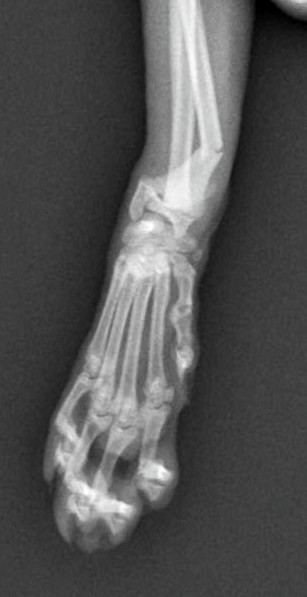

5~6歳以上の去勢手術をしていないオス犬に多い病気ですが、メス犬や去勢した犬に起こることもあります。お尻の筋肉が萎縮した結果、筋肉の隙間から直腸や膀胱が皮膚の下にとびでてしまいます。これにより便が出にくくなったり膀胱炎になったりします。手術をすることで機能回復および今後の致死的な状況を回避することができます。当院では去勢手術→結腸固定→前立腺固定→骨盤隔膜構成筋の縫縮→内閉鎖筋フラップ→浅臀筋フラップの順で通常腹側・臀部左右両側同時に行います。また老化以外に、筋肉が萎縮する原因があったり、腹圧がかかる原因があったりする場合も多いので、再発防止のためそれらの診断・治療も重要です。今回のワンちゃんも無事手術も終わり元気に退院しました。よかったね。